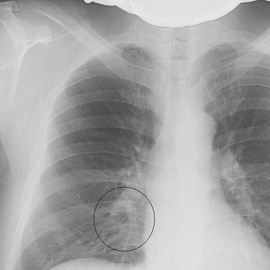

Подтверждается диагноз проведением рентгенографии и анализом крови. Выявление возбудителя и определение его чувствительности к антибиотикам проводят при баканализе мокроты.